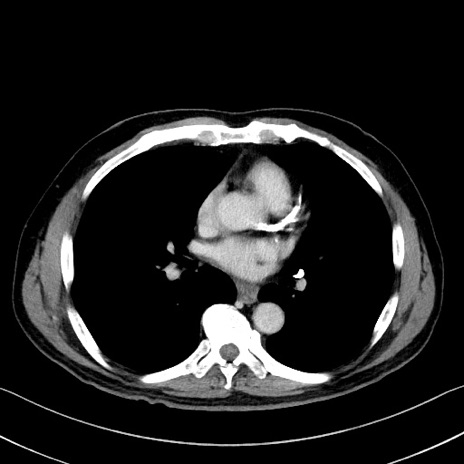

症例35(横断像)

【症例】70歳代 男性

【主訴】腹部膨満、嘔吐

【現病歴】昨日より腹部膨満感出現。本日増悪し、仙痛出現。嘔吐あり、受診。

【既往歴】糖尿病、胆摘後

【身体所見】BP 149/80mmHg、HR 74/min、BT 35.9℃、腹部:膨満、軟、圧痛なし。腸雑音減弱あり。上腹部正中切開瘢痕あり。

【データ】WBC 13500、CRP 1.72